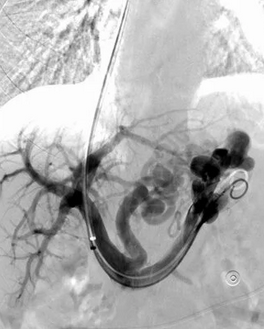

CT Angiography. Presence of a ruptured pseudoaneurysm of the common hepatic artery (Courtesy Dr. V. Penopoulos)